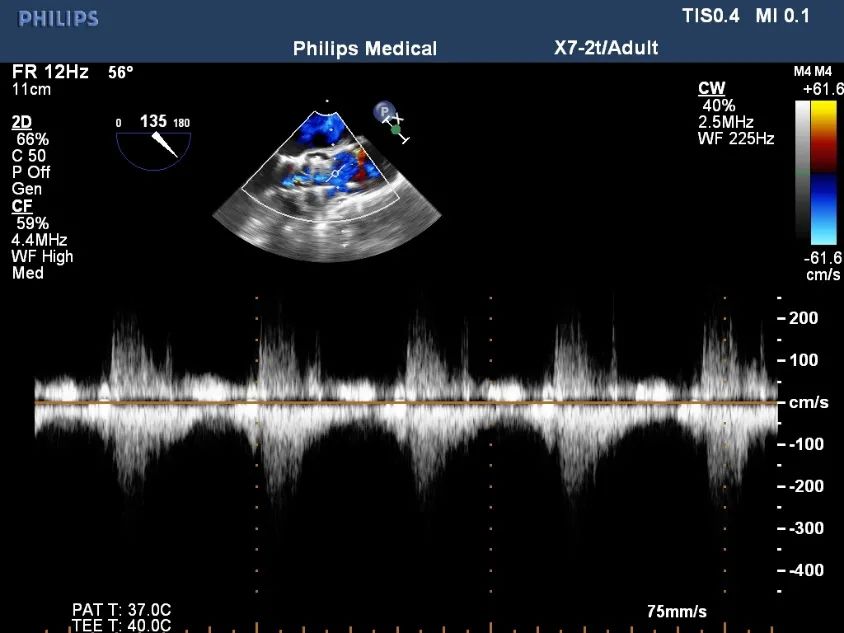

超声影像

TEE影像,烟囱支架显影清晰,支架内血流通畅